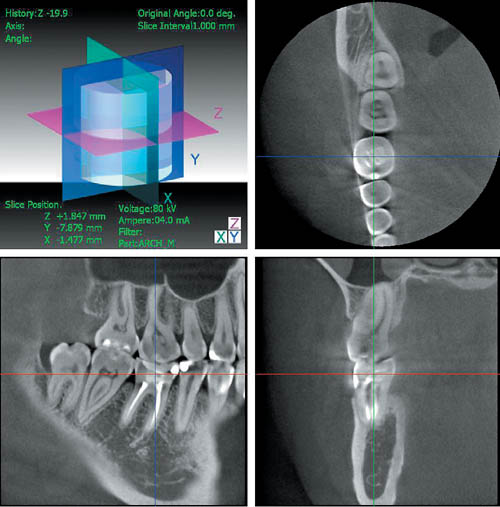

— позволяет проводить оценку результатов ортопедического и ортодонтического лечения стоматологических пациентов

(рис. 6);